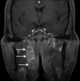

Enlarged lateral retropharyngeal lymph node